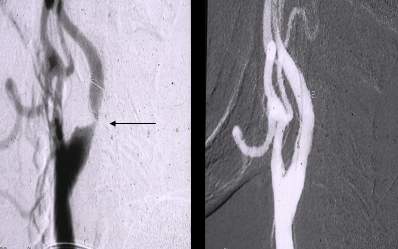

Figure 4. Primary stenting of an 80-90% stenosis on the distal portion of the left common iliac artery distal stenosis. Left and middle panel: stenosis is indicated by the arrow. Contrast medium was given from the aorta proximal to the stenosis (left panel) or the left common iliac artery distal from the stenosis.

Due to technical reasons (antegrade or retrograde puncture, contralateral or ipsilateral puncture, femoral or brachial puncture), prognosis and risks, three types of levels are distinguished: iliac (Figure 4), femoro-popliteal (Figure 5) and crural (infragenual) (Figure 6) endovascular therapy. The latter two composes the infrainguinal group. PTA and stent placement are usually technically easier (with the exception of long occlusions), have a longer patency and carry lower risk in the iliac group compared to the other two groups. Patency following crural PTA is the worse and carries the highest risk, therefore, it is usually indicated only in Fontaine stages III and IV. The number of amputation per capita in Hungary is larger than that in most other European countries. In patients with gangrene and diabetes mellitus, crural PTA may save a large number of amputations. In case of successful PTA, limb salvage rate is considerably higher than crural patency rate, since perfusion needed for a healing ulcer or gangrene is considerably higher than for the basic functions (collateral arteries may be sufficient for such purpose). Subintimal PTA is performed more and more frequently: when luminal recanalisation is technically not possible, intentional dissection is done using the hydrophilic guidewire along the occluded segment; then, distally to the occlusion, the guidewire is directed back to the normal lumen and a new channel is formed along the normal lumen–dissected channel–normal lumen route (Figure 5).

Figure 5. Subintimal percutaneous transluminal angioplasty (PTA). Panel A: Superficial femoral artery has been occluded from its origin with a stump (upper arrow). Refilling occurs at the distal SFA (lower arrow), total length of the occlusion is approximately 18 cm. Panel B: The white background („roadmap”) shows the profunda femoral artery. The guidewire (in black on the white background; arrow) is at the beginning of the occluded segment. Panel C: the guidewire forms a loop (arrow), and gradually proceeds into the subintimal space. Panel D: the tip of the guidewire reached the normal popliteal artery lumen, there is no loop formation any longer. Panel E: Following balloon dilation of the whole segment, SFA shows quick flow in its entire length.